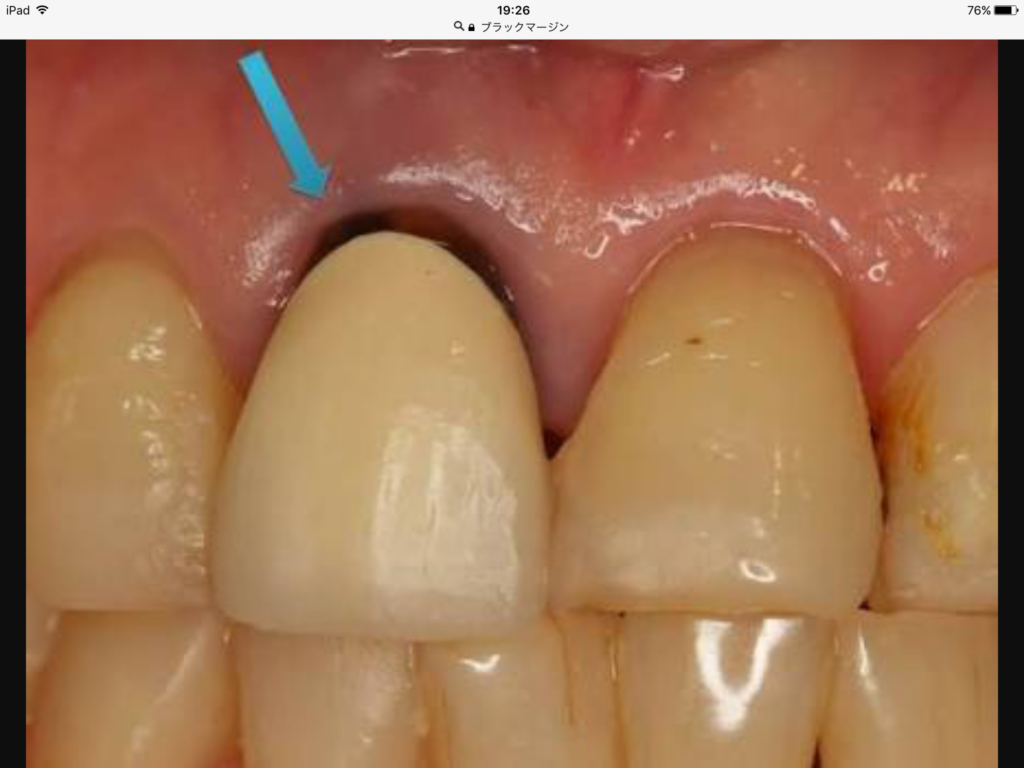

皆さんは、ブラックマージンと言うのうを聞いた事ありますか⁇

写真だとこんなに感じです

これは、型取りするときに

歯茎の状態がきちんと整っていないのに

歯茎が腫れたまま型取りしたので結果

その状態で被せ物が出来ていて

つけたときは大丈夫でも、時間が経ち歯茎が正常に戻っていくと

腫れてた部分に隙間が生じてしまうのでこのような黒いラインが出来てしまうのです。